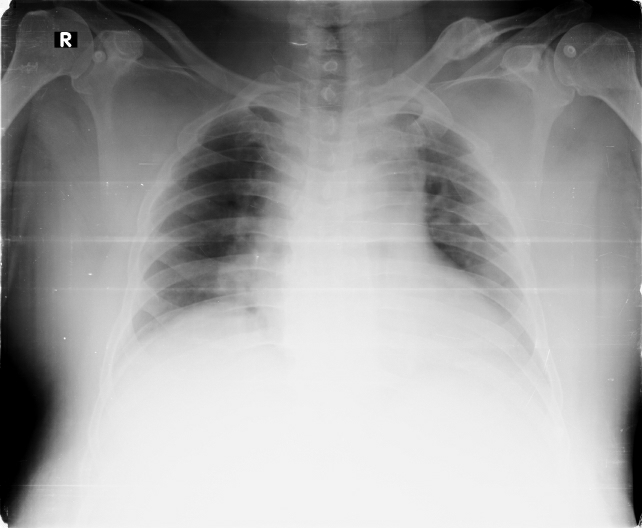

chest x ray